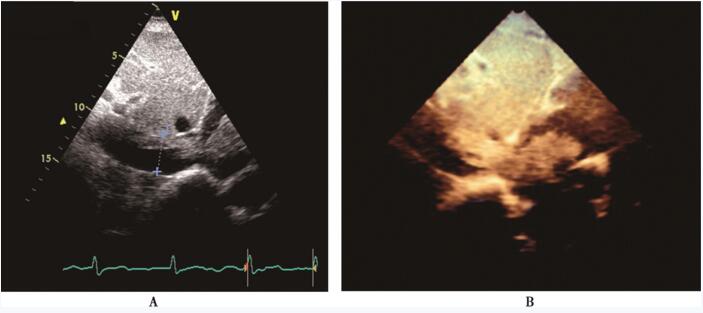

超声心动图:右心房内可见实性强回声团块(图85-1),该团块自下腔静脉延续至右心房内 (图85-2),收缩期突入右心室,舒张期回纳至右心房;下腔静脉近心端可见两束条索样回声,与上述右心房内占位性病变相连续;彩色血流多普勒显示收缩期三尖瓣房侧见大量反流信号。超声诊断:心内平滑肌瘤病。

图85-2 超声心动图提示下腔静脉内占位性病变延续至右心房 A:剑突下切面示下腔静脉增宽约30mm,下腔静脉内占位性病变延续至右心房; B:三维超声心动图示下腔静脉内占位性病变向右心房延续